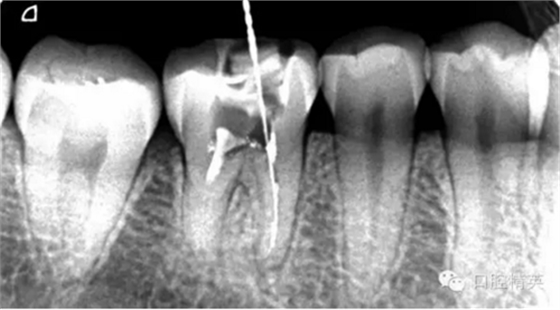

疏通其余三根30分鐘。

近中試尖,超出,這是沒有很好的把握工作長度,這是自己在預備時可能出現(xiàn)超預備的情況,所以以后機括預備一定要注意,防止超預備,否則會導致術(shù)后疼痛。